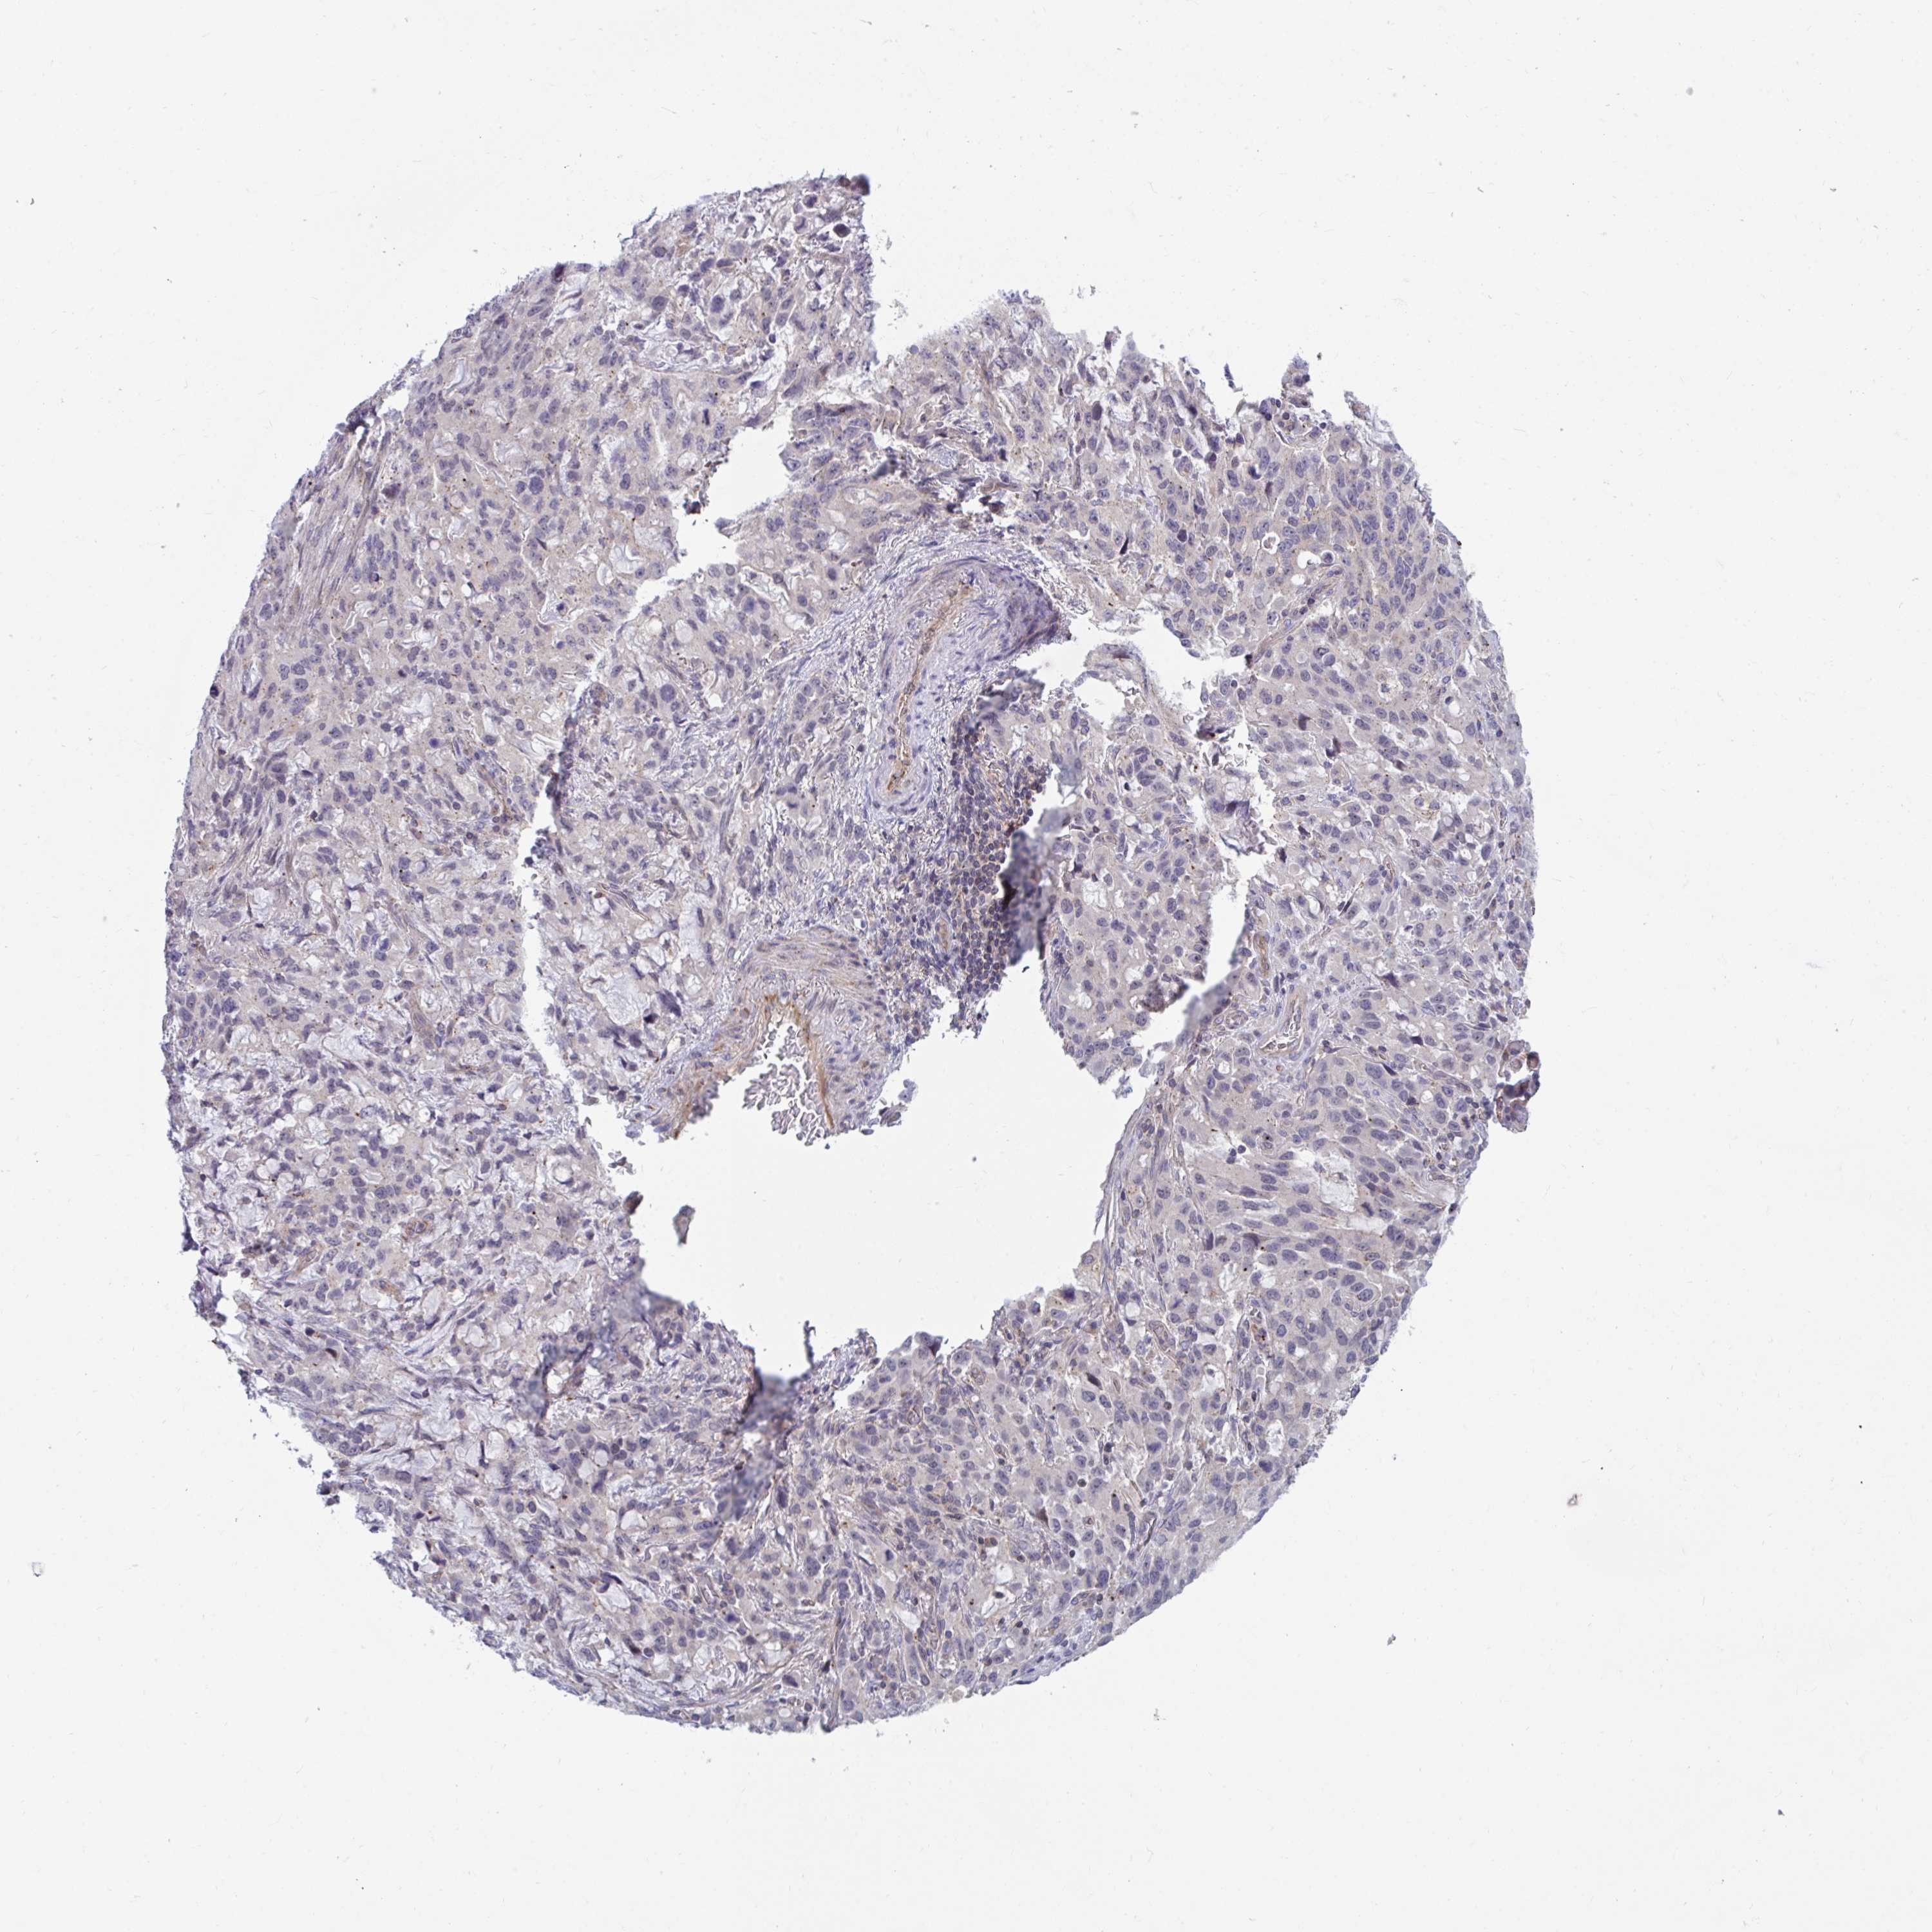

STOMACH CANCER - Protein expressioni

A mouse-over function shows sample information and annotation data. Click on an image to view it in a full screen mode. Samples can be filtered based on level of antibody staining by selecting one or several of the following categories: high, medium, low and not detected. The assay and annotation is described here.

Note that samples used for immunohistochemistry by the Human Protein Atlas do not correspond to samples in the TCGA dataset.

Antibody stainingi

Antibody staining in the annotated cell types in the current human tissue is reported as not detected, low, medium, or high, based on conventional immunohistochemistry profiling in selected tissues. This score is based on the combination of the staining intensity and fraction of stained cells.

Each image is clickable and will lead to virtual microscopy that enables deeper exploration of all samples and also displays staining intensity scores, fraction scores and subcellular localization as well as patient and tissue information for each sample.

Antibody HPA041802

Antibody HPA054532

Staining

High

Medium

Low

Not detected

Intensity

Strong

Moderate

Weak

Negative

Quantity

>75%

75%-25%

<25%

None

Location

Nuclear

Cytoplasmic/membranous

Cytoplasmic/membranous,nuclear

Adenocarcinoma, NOS

Adenocarcinoma, High grade